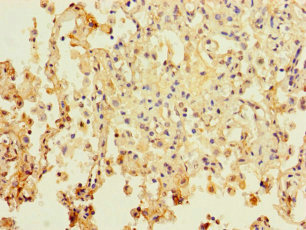

應用范圍:ELISA, IHC

Application Recommended Dilution IHC 1:20-1:200 -